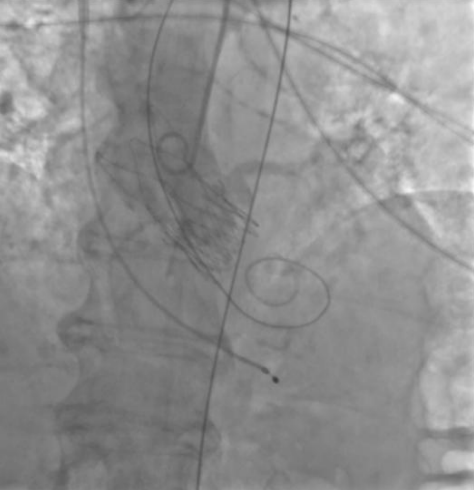

Процедура ТИАК выполнялась по стандартной методике, принятой в нашем центре (рис. 1, 2). Поскольку согласно инструкции производителя перед имплантацией выбранного вида протеза необходимо выполнить предварительную вальвулопластику АК, была выполнена предилатация баллонным катетером 20×40 мм. После выполнения вальвулопластики у пациентки развилась тяжелая аортальная регургитация c падением гемодинамики до систолического АД 40 мм рт.ст. Поэтому было принято решение оперативного заведения, позиционирования и имплантации "ACURATE Neo 2" диаметром 23 мм в аортальную позицию с целью купирования регургитации и стабилизации гемодинамики. Однако после имплантации протеза состояние пациентки продолжило ухудшаться — развилась фибрилляция желудочков. Дальнейшие реанимационные мероприятия в течение 40 мин — без успеха. При аортографии отмечалось отсутствие подвижности створок протеза с сохраняющейся тяжелой регургитацией. После чего была констатирована биологическая смерть больной.

Рис. 1. Пациентка А. Ангиография корня аорты — аортальная регургитация после баллонной предилатации.

Рис. 2. Пациентка А. В момент проведения протеза визуализируется массивная аортальная регургитация.

В представленных клинических случаях по данным ЭхоКГ у всех пациенток наблюдался феномен малого объема ЛЖ (табл. 1), однако подход к проведению оперативного вмешательства различался. Так, у первой пациентки причиной неудачной ТИАК послужила сложившаяся совокупность факторов. Развившийся гемодинамический коллапс можно объяснить тем, что, вероятно, произошла объемная перегрузка ЛЖ за счет возросшей аортальной регургитации (подтверждается при выполнении аортографии (рис. 1), что в сочетании с малой полостью и диастолической дисфункцией привело к молниеносному развитию острой левожелудочковой недостаточности. В Клинических рекомендациях по ХСН (2024) подчеркивают, что у пациентов с диастолической дисфункцией и малым объемом ЛЖ риск гемодинамического коллапса значительно возрастает, особенно при наличии сопутствующей легочной гипертензии [8]. В тот момент единственным возможным решением сложившейся ситуации стало быстрое заведение и установка биопротеза. Однако даже после имплантации клапана восстановления гемодинамики не произошло. При развитии подобного сценария выполняется продвинутая сердечно-легочная реанимация (СЛР), при этом краеугольным камнем успешной СЛР у пациентов после имплантации протеза является выполнение качественных компрессий, позволяющих создать достаточное пульсовое давление, необходимое для обеспечения запирательной функции протеза и разгрузки ЛЖ. К сожалению, наличие кифосколиотического изменения грудного отдела позвоночника не позволили выполнять эффективные компрессии ни мануально, ни с помощью механического устройства для непрямого массажа сердца, вследствие чего наступившая острая левожелудочковая недостаточность не была скомпенсирована работой протеза клапана, что и привело к летальному исходу. Данные аутопсии лишь подтверждают изложенную версию произошедших событий. Также нельзя исключить влияния сопутствующей желудочковой фибрилляции и выраженной легочной гипертензии на развитие неблагополучного течения ТИАК.